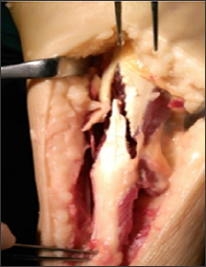

Figure 3: The gap of ruptured tendon after debridement.

Figure 4: Inverted V shaped incision of the tendinous portion of the proximal stump.

All cases were operated under spinal anesthesia, tourniquet was applied to the affected limb, postero-medial approach was used and centered over the site of the rupture (Figure 2). All scar tissues were debrided, keeping surrounding tissues and approaching healthy margins of the Achilles tendon, and exploration of plantaris tendon is performed. The gap between both ends was measured with the ankle at 30 degrees planter flexion after debridement and excision of scar tissues were 5-7 cm (mean 5.6 cm) (Figure 3). An inverted V shape incision was done in the proximal tendinous portion of the proximal stump; the length of the limb is 1.5 times the length of the gap (Table 1) (Figure 4). The proximal stump is pulled down, with the ankle in 30 degrees planter flexion and repaired to the distal stump with Krackow method using non-absorbable sutures (Demo-bond no 5). Then the plantaris was harvested using tendon stripper and used to augment the repair (Figures 5 & 6) Closure of the wound and above knee cast in 20 degrees planter flexion was applied.